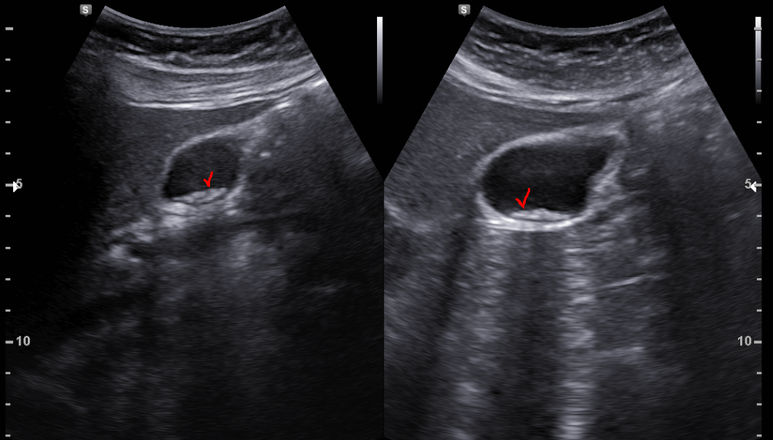

초음파 시행; 후방 음영 소실을 보이는 작은 담석들이 관찰됨

자세 변화에 따라 이동하는 모습